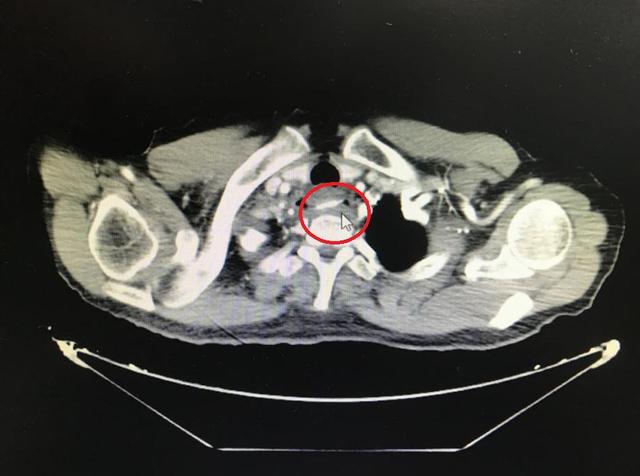

一顿饭后 , 林先生感觉有鱼刺卡在喉咙 , 便强吞两口饭、咽下鱼刺 。 两天后 , 他突感剧烈胸痛 , 至武汉大学人民医院急诊科就诊 。

检查发现 , 鱼刺像一把圆月弯刀 , 横插在食管和胸主动脉附近 , 已刺穿食管壁 。 如果盲目拔出 , 必定会形成主动脉破口 。 胸主动脉是人体最粗大的动脉血管 , 压力很高 。 一旦形成破口 , 出血犹如“大坝决堤”一般 , 难有抢救机会 。

文章插图

在医疗部组织下 , 医院胸外科、心血管外科、耳鼻喉-头颈外科、消化内科、介入科、放射科、麻醉科等10个科室30位专家 , 紧急讨论 , 认为必须马上将鱼刺取出 。 如果任其留在体内继续感染 , 林先生将失去最后的机会 。

专家团队确定微创取刺手术方案 。 但没想到 , 上了手术台 , 内镜反复探查 , 术前本已定位精确的鱼刺 , 不见了!

专家团队判断 , 很有可能是术前随食道蠕动 , 或主动脉内血流强劲冲击 , 这根鱼刺穿出食管进入胸腔甚至主动脉 。 此时已没有微创取刺的可能 , 必须尽快开胸探查将鱼刺取出 。

手术方案立即调整 。 胸外科黄杰教授团队接力上台 。 果然 , 鱼刺穿出食管 , 几乎整个扎进主动脉内 , 仅在外露出3毫米的刺尖 。